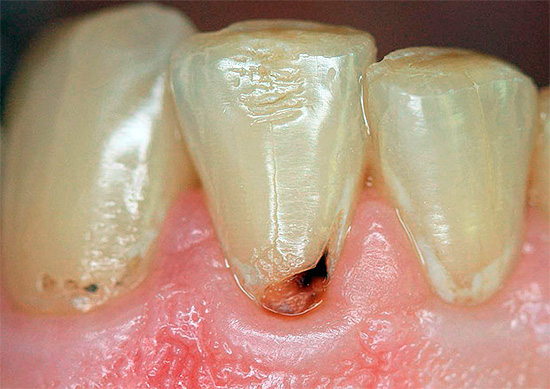

Poiché la carie di cemento è spesso combinata con la carie cervicale, per i denti anteriori, oltre ai rischi menzionati, questo è anche pieno di estetica. Macchie scure o carie cavità sui denti anteriori, specialmente se non vengono eliminati per diversi anni, provocano spesso complessi psicologici, problemi sul lavoro e nella comunicazione con il sesso opposto.

Con la posizione aperta della carie di cemento sui denti anteriori in combinazione con la carie cervicale, di norma, già allo stadio di un punto cariato senza una cavità cariata e nessun sintomo, si possono sospettare seri problemi e consultare un medico. Inoltre, in questo caso stiamo parlando della comodità di comunicare con i propri cari, amici, colleghi e altre persone. La comparsa di punti scuri, una sfumatura gessosa di smalto, le sue crepe e le schizzi al bordo con la gomma consentono di determinare la carie di cemento nella fase iniziale di sviluppo, quando può ancora "sfondare" nell'area subgengivale.

Con estese cavità carie che si estendono dalla superficie esterna del dente più in profondità nelle gengive, si verificano solitamente reazioni a freddo, caldo, dolce, acido, nonché una sensazione di indolenzimento, dolore durante il cibo. Spesso la gomma si allontana dal dente così tanto che sotto di esso è visibile l'area interessata del cemento radicolare e la radice stessa. In tali casi, è necessario consultare immediatamente uno specialista per ulteriori studi e conferma della diagnosi.